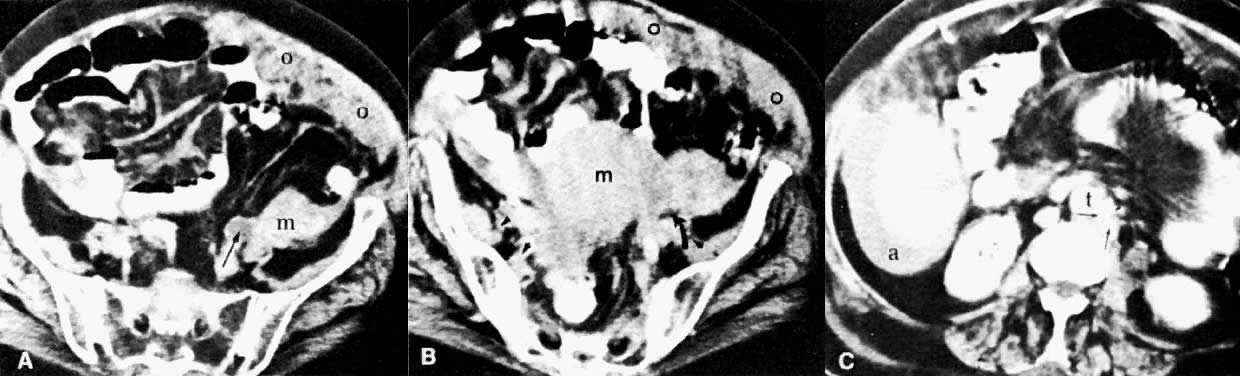

Currently ultrasound, CT, and MRI have replaced EU for the detection of urinary tract obstruction. Both CT and MRI can accurately demonstrate local tumor spread. CT has been shown to be superior to EU in the evaluation of the urinary system.24,110,111 Although the specificity of EU ranges from 79% to 97%, its sensitivity ranges from 7% to 33% in depicting the spread of malignant diseases.110 EU demonstrates the course and caliber of the ureters, but it is inaccurate in diagnosing nonobstructive extension of malignancy to the ureter. The superiority of CT is more noticeable in stage IIB cervical cancer and at more advanced stages.24 CT not only can diagnose ureteral obstruction, but also can detect its level and cause. In one study, ureteral involvement without hydronephrosis was detected in 21% of cases (see Fig. 11).9 CT can also demonstrate involvement of unopacified obstructed ureters (Fig. 38A and Fig. 38B).

Fig. 38. Stage III ovarian adenocarcinoma with ureteral invasion and omental cake. A and B. Serial CT scans of the pelvis 2 cm apart show a large, irregular pelvic mass ( m ). A thick layer of inhomogeneous soft tissue is seen under the anterior abdominal wall consistent with omental involvement ( o ). Note the dilated and unopacified left ureter ( long arrow) in A and the pinching of the ureter by the pelvic mass ( curved arrow) in B. Tumor extension to the pelvic sidewall is seen in B( arrowheads ). C. CT scan of the abdomen shows several small, confluent para-aortic lymph nodes consistent with metastases ( short arrows ). ( t, aorta; a, ascites.)